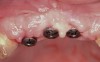

Figure 17  The extraction sites of tooth Nos. 9 and 10 were obturated with rhBMP-2/ACS. The presence of a portion of the facial cortex provided space maintenance for bony regeneration. The same biomaterial was placed into site Nos. 7 and 8, but a resorbable PLGA mesh was contoured over the site and fixed to the facial bone to provide regenerative space in this area.

Figure 17